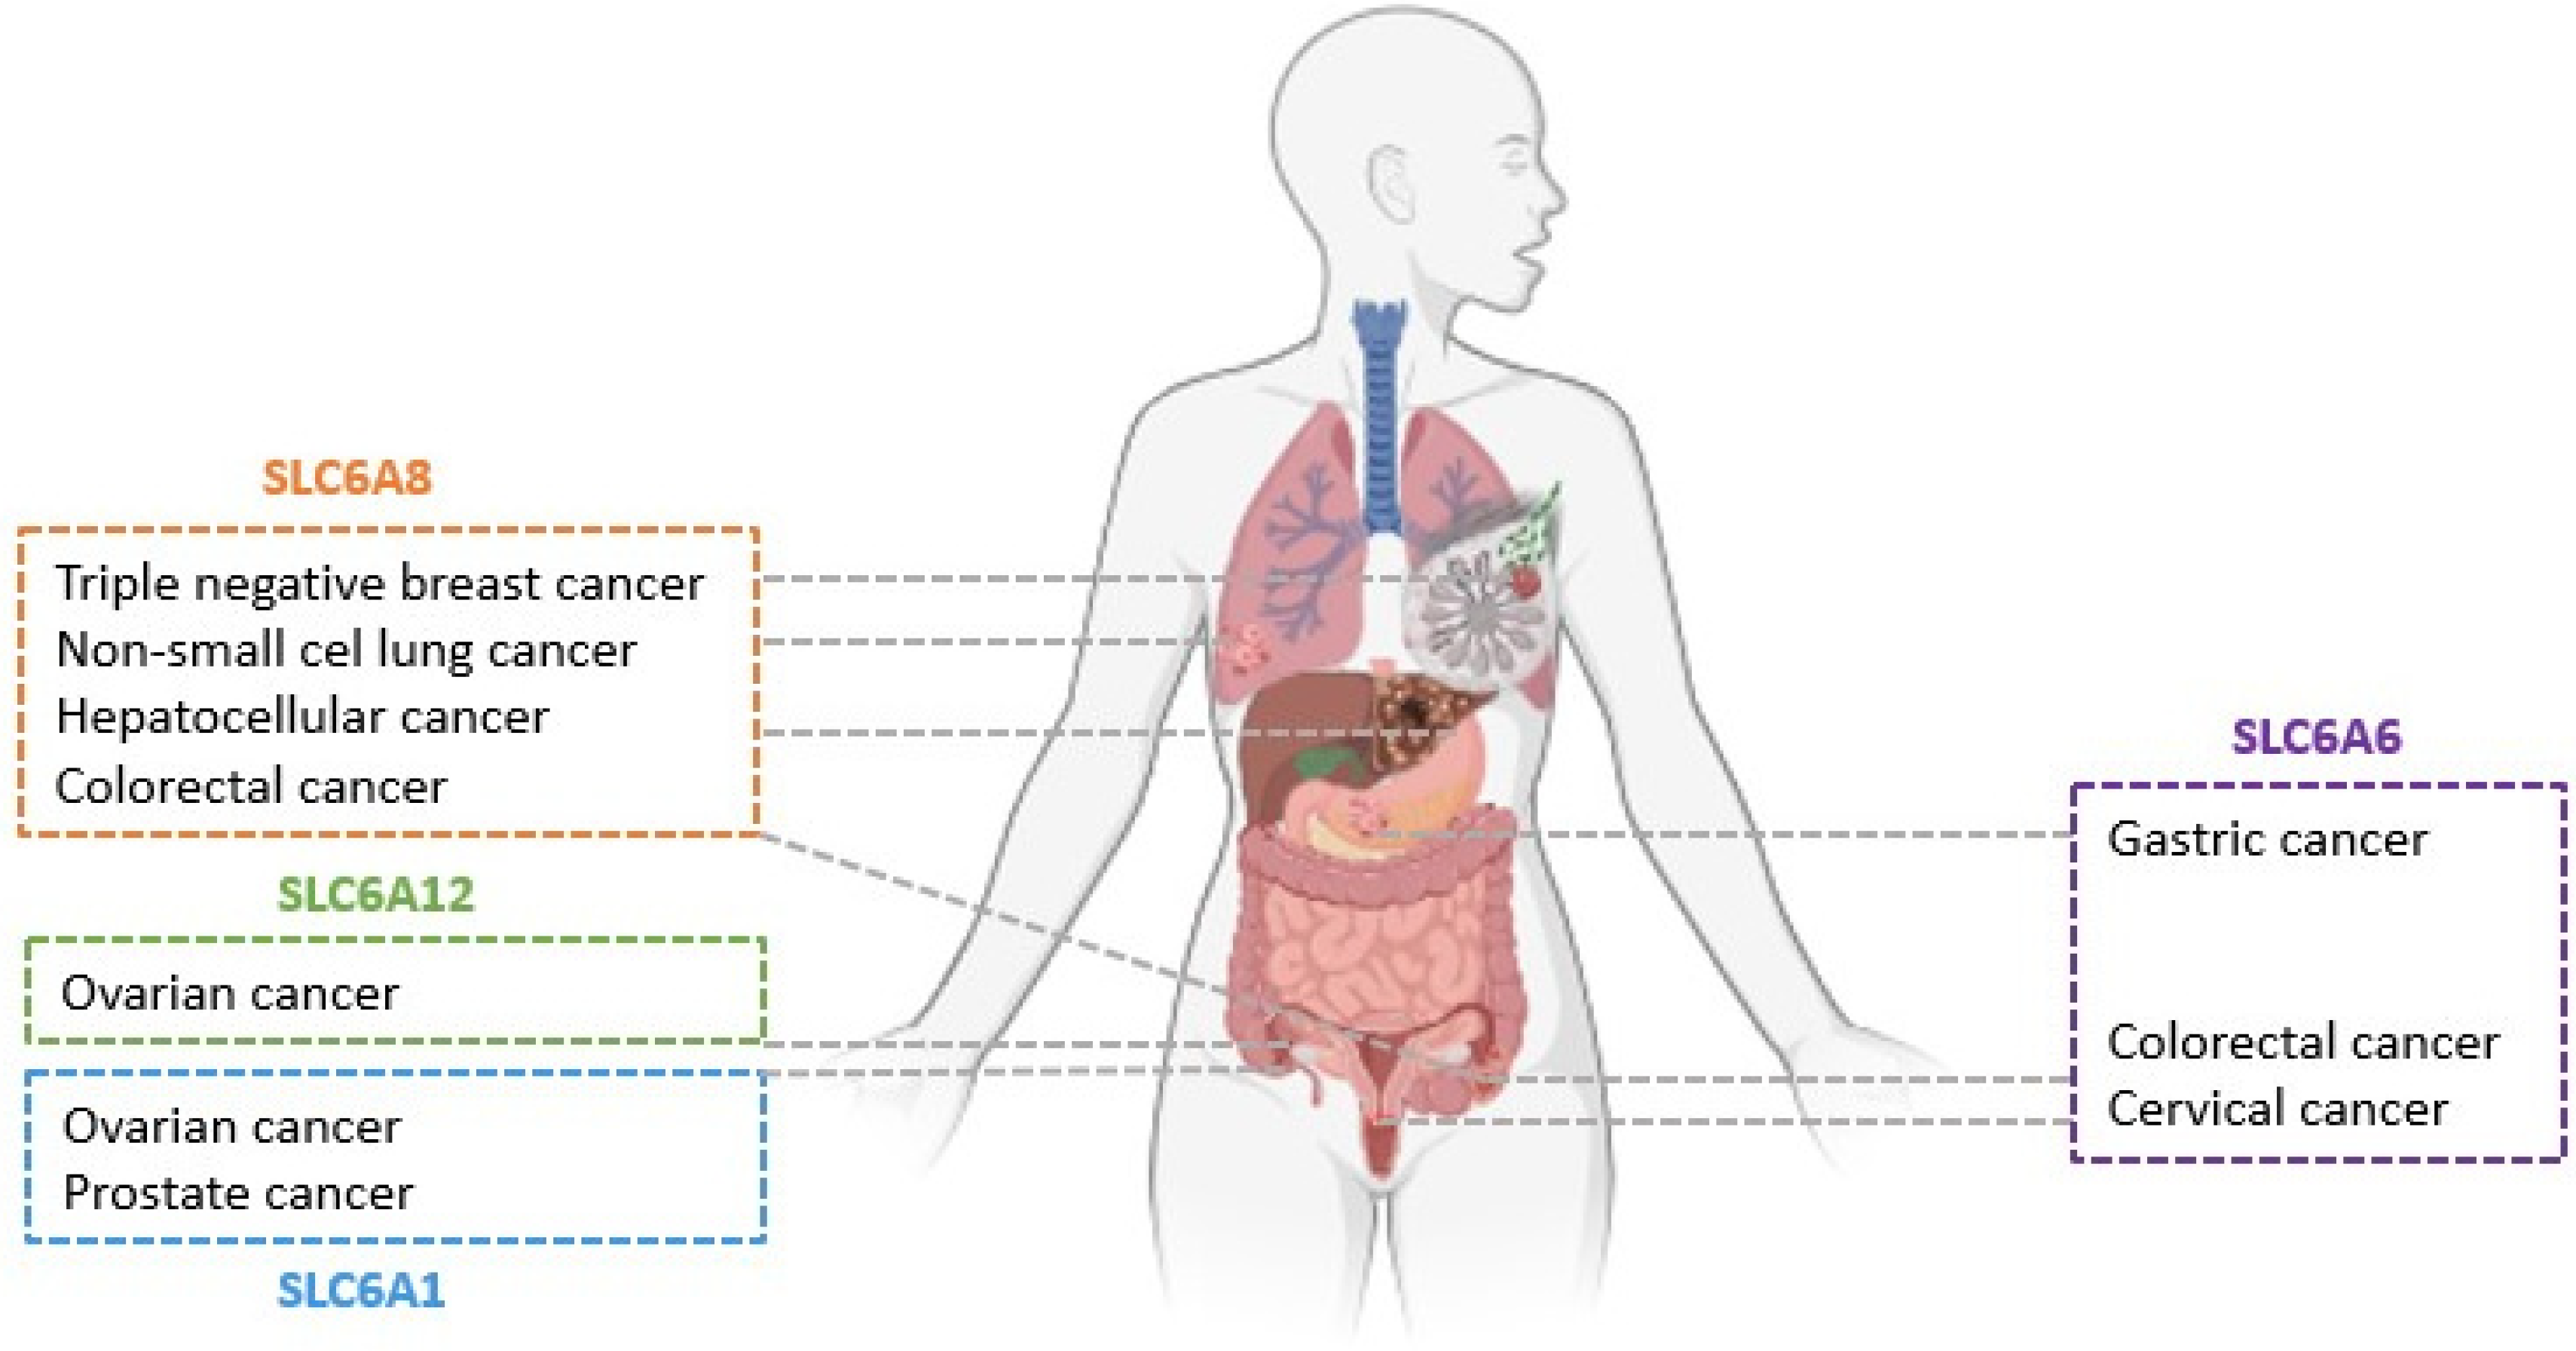

:1. Introduction

- Zhao, Y.; Zhou, X.; He, Y.; Liao, C. SLC6A1-miR133a-CDX2 loop regulates SK-OV-3 ovarian cancer cell proliferation, migration and invasion. Oncol. Lett. 2018, 16, 4977–4983. [Google Scholar] [CrossRef]

- Chen, C.; Cai, Z.; Zhuo, Y.; Xi, M.; Lin, Z.; Jiang, F.; Liu, Z.; Wan, Y.; Zheng, Y.; Li, J.; et al. Overexpression of SLC6A1 associates with drug resistance and poor prognosis in prostate cancer. BMC Cancer 2020, 20, 289. [Google Scholar] [CrossRef]

- Sung, H.Y.; Yang, S.-D.; Park, A.K.; Ju, W.; Ahn, J.-H. Aberrant Hypomethylation of Solute Carrier Family 6 Member 12 Promoter Induces Metastasis of Ovarian Cancer. Yonsei Med. J. 2017, 58, 27. [Google Scholar] [CrossRef]

- Wang, D.; Du, J.; Ren, C.; Zhou, M.; Xia, Z. Elevated SLC6A6 expression drives tumorigenesis and affects clinical outcomes in gastric cancer. Biomark. Med. 2019, 13, 95–104. [Google Scholar] [CrossRef]

- Yasunaga, M.; Matsumura, Y. Role of SLC6A6 in promoting the survival and multidrug resistance of colorectal cancer. Sci. Rep. 2014, 4, 4852. [Google Scholar] [CrossRef] [PubMed]

- Xia, Y.F.; Pei, G.H.; Wang, N.; Che, Y.C.; Yu, F.S.; Yin, F.F.; Liu, H.X.; Luo, B.; Wang, Y.K. MiR-3156-3p is downregulated in HPV-positive cervical cancer and performs as a tumor-suppressive miRNA. Virol. J. 2017, 14, 20. [Google Scholar] [CrossRef] [PubMed]

- Feng, Y.; Guo, X.; Tang, H. SLC6A8 is involved in the progression of non-small cell lung cancer through the Notch signaling pathway. Ann. Transl. Med. 2021, 9, 264. [Google Scholar] [CrossRef] [PubMed]

- Fan, Y.; Zhou, Y.; Lou, M.; Gao, Z.; Li, X.; Yuan, K. SLC6A8 is a Potential Biomarker for Poor Prognosis in Lung Adenocarcinoma. Front. Genet. 2022, 13, 845373. [Google Scholar] [CrossRef] [PubMed]

- Li, Q.; Liu, M.; Sun, Y.; Jin, T.; Zhu, P.; Wan, X.; Hou, Y.; Tu, G. SLC6A8-mediated intracellular creatine accumulation enhances hypoxic breast cancer cell survival via ameliorating oxidative stress. J. Exp. Clin. Cancer Res. 2021, 40, 168. [Google Scholar] [CrossRef] [PubMed]

- Yuan, L.; Wu, X.J.; Li, W.C.; Zhuo, C.; Xu, Z.M.; Tan, C.; Ma, R.H.; Wang, J.C.; Pu, J. SLC6A8 Knockdown Suppresses the Invasion and Migration of Human Hepatocellular Carcinoma Huh-7 and Hep3B Cells. Technol. Cancer Res. Treat. 2020, 19, 1533033820983029. [Google Scholar] [CrossRef]

- Kurth, I.; Yamaguchi, N.; Andreu-Agullo, C.; Tian, H.S.; Sridhar, S.; Takeda, S.; Gonsalves, F.C.; Loo, J.M.; Barlas, A.; Manova-Todorova, K.; et al. Therapeutic targeting of SLC6A8 creatine transporter suppresses colon cancer progression and modulates human creatine levels. Sci. Adv. 2021, 7, eabi7511. [Google Scholar] [CrossRef]

- Stary, D.; Bajda, M. Taurine and Creatine Transporters as Potential Drug Targets in Cancer Therapy. Int. J. Mol. Sci. 2023, 24, 3788. [Google Scholar] [CrossRef] [PubMed]